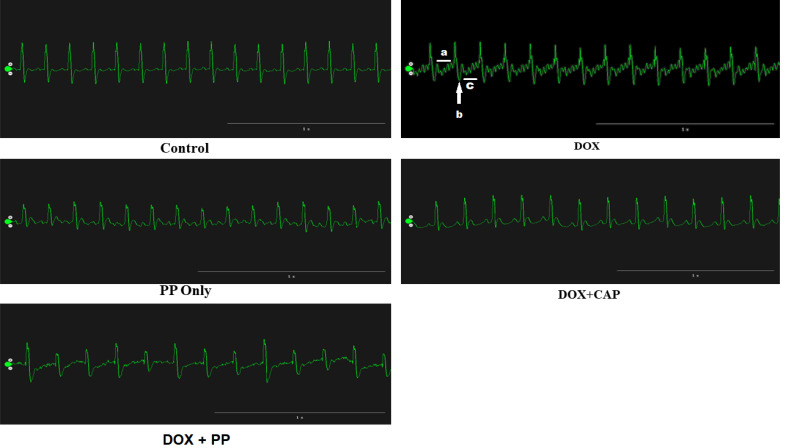

Results: The results revealed a significant (p < 0.01) elevation of T-wave and altered electrocardiographic parameters in the doxorubicin group than the control, P. pellucida, and other experimental groups. The heart rate, cardiac troponin level, lactate dehydrogenase, creatine kinase, angiotensin-converting enzyme activities, and inflammatory biomarkers were significantly (p < 0.01) higher while nitric oxide level was significantly (p < 0.05) reduced in the doxorubicin-only group compared to the control. Cardiac cell hypertrophy and inflammatory cell infiltration were observed due to doxorubicin administration. Treatment with P. pellucida extract and captopril reversed these trends and improved the antioxidants and inflammatory activities.

Conclusion: Peperomia pellucida extract improves electrocardiographic pattern, has cardioprotective ability, and prevents doxorubicin-induced myocardial injury probably due to its phytochemical constituents and anti-inflammatory properties.